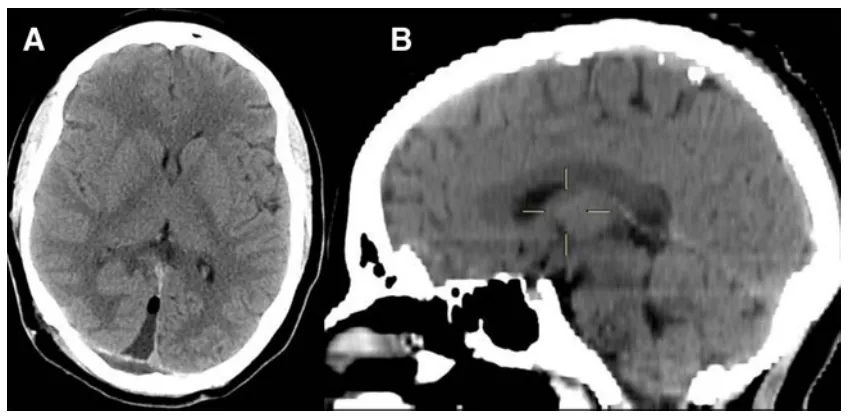

未曾预料,宝贝女儿偶尔提到的头痛、怕光、视物模糊,根源竟在于颅内病变。MRI检查显示豆豆的松果体区存在一直径13毫米的囊肿。

复查MRI时,医生微微皱眉:"囊肿已增长至16毫米,虽仅增大3毫米,但结合症状加重,建议手术干预。"

术后过程平稳,豆豆仅出现短暂视力模糊,24小时内自行恢复。病理检查提示为松果体囊肿,周围可见毛细胞样胶质层包绕。术后6个月随访显示豆豆头痛无复发,恢复良好。